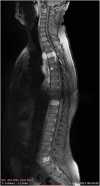

Methods: A 39-year-old man presented with signs of spinal cord compression for the past 2 weeks. His medical history was consistent for an asymptomatic right iliac wing mass that appeared 3 years ago and for which he has not consulted. Magnetic resonance imaging revealed multiple bony lesions of the thoraco-lumbar spine associated with a 6-cm right paravertebral mass at the T4 level extending posteriorly through the intervertebral foramina to the spinal canal causing major spinal cord compression. An emergent T2-T6 laminectomy allowed for a complete resection of the epidural mass. Pathological examination confirmed the diagnosis of well-differentiated liposarcoma. Adjunctive radiation therapy was administered.